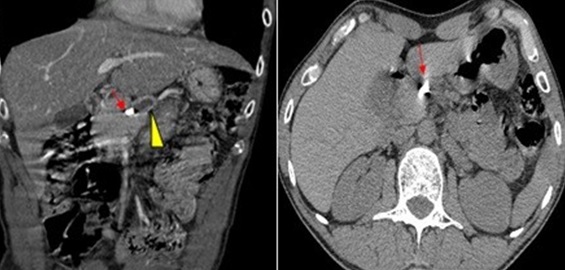

Les calculs pancréatiques sont le plus souvent mis en évidence chez les malades atteints de pancréatite chronique. En l'absence de PC, ils peuvent être observés en amont d'une tumeur, ou d'une sténose canalaire. Ils peuvent être associés à une augmentation du diamètre du canal de Wirsung et à une sclérose irrégulière de la glande associée à une perte du tissu acineux, remplacé par du tissu graisseux. Nous rapportons l'observation d'un patient de 43 ans chez lequel des epigastralgies ont conduit à la découverte d'un énorme calcul unique, calcifié et obstructif du canal de Wirsung avec pancréatite chronique d'amont. Les investigations complémentaires ont permis de confirmer le caractère apparemment primitif de la lithiase. Un homme âgé de 43 ans consultait aux urgences pour des douleurs épigastriques atypiques évoluant depuis 3 mois. Il n'existait pas d'antécédents personnel ni familiaux de maladie du pancréas notamment pas de notion d'alcoolisme. L'examen clinique était normal. La numération formule sanguine, l'ionogramme sanguin, le bilan hépatique, l'électrophorèse des protéines, le dosage de la CRP, la parathormone, l'amylasémie, la lipasémie, la calcémie et la phosphorémie étaient normaux. La tomodensitométrie abdominale a permis de mettre en évidence un calcul unique dans le canal de Wirsung à la jonction isthmo-corporéale mesurant 6 mm. Le parenchyme pancréatique était atrophié. La vésicule et la voie biliaire principale étaient normales. L'opacification rétrograde du Wirsung, a permis d'affirmer l'absence de pancréas divisum ou d'une autre malformation canalaire pancréatique permettant ainsi l'extraction du calcul après cathétérisme du Wirsung avec une bonne évolution post CPRE.